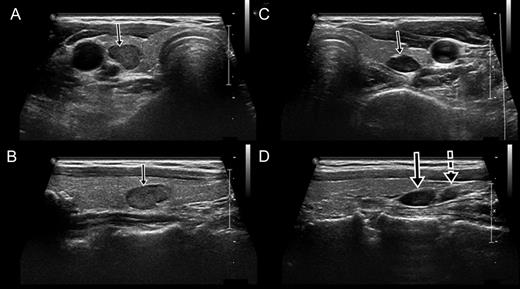

Sonography showed the right parathyroid gland within the thyroid and the adjoining left parathyroid glands. (A) Transverse view of the right parathyroid gland within the thyroid (arrow). (B) Longitudinal view of the right parathyroid gland (arrow). (C) Transverse view of the left superior parathyroid gland. (D) Longitudinal view of the left superior (arrow) and inferior (dotted arrow) parathyroid glands. The left superior parathyroid had migrated to an inferior position.